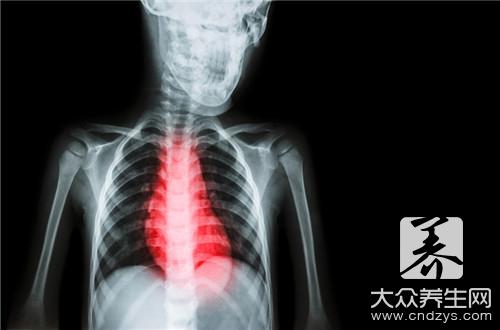

很多疾病的发现和检查并不是只通过医生简单的检查,还需要通过很多仪器甚至是实验的检查,因为人体太过于奥妙,很多时候并不是头痛医头,尾痛医尾...